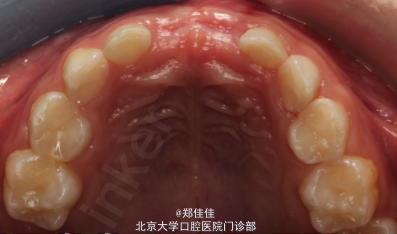

5ys F 主诉:左上前牙外伤后1周 现病史:约1周前,患者上前牙撞于浴缸上,否认头晕恶心及意识丧失,有牙龈出血,曾于外院就诊,给予“消炎药”,否认牙齿自发痛,有牙齿松动

51牙冠切端位于龈上约3mm,叩痛(+),IIO松动,龈缘略肿 X线片示51龈向移位,根周膜增宽,未见明显根折线,下方11恒牙胚在,Nolla6期,表面硬骨板欠连续完整 61牙冠切端与62平齐,叩痛(+),IO松动,牙龈未见明显异常 X线片示61根尖周密度减低,见牙根外吸收影,下方21恒牙胚在,Nolla5期,表面硬骨板欠连续完整

初诊印象:51,61挫入 治疗设计:1.51拔除 2.61定期复查,必要时拔除 处置:1.签知情同意书 2.51STA必兰局麻下分龈,挺松,钳拔,离体牙完整,复位,压迫,止血

2个月后复查,61根尖脓肿拔除 讨论:乳前牙挫入的治疗 乳牙嵌入牙槽不应拉出复位,以避免二次创伤或通过牙龈沟和牙周间隙造成感染。本病例中建议拔除51,61,但患者家长希望尽量保留牙齿,于是拔除51,观察61.乳牙外伤后发生牙髓坏死,根尖感染或牙槽脓肿应及时拔牙。于是当61出现根尖周炎时及时拔除。